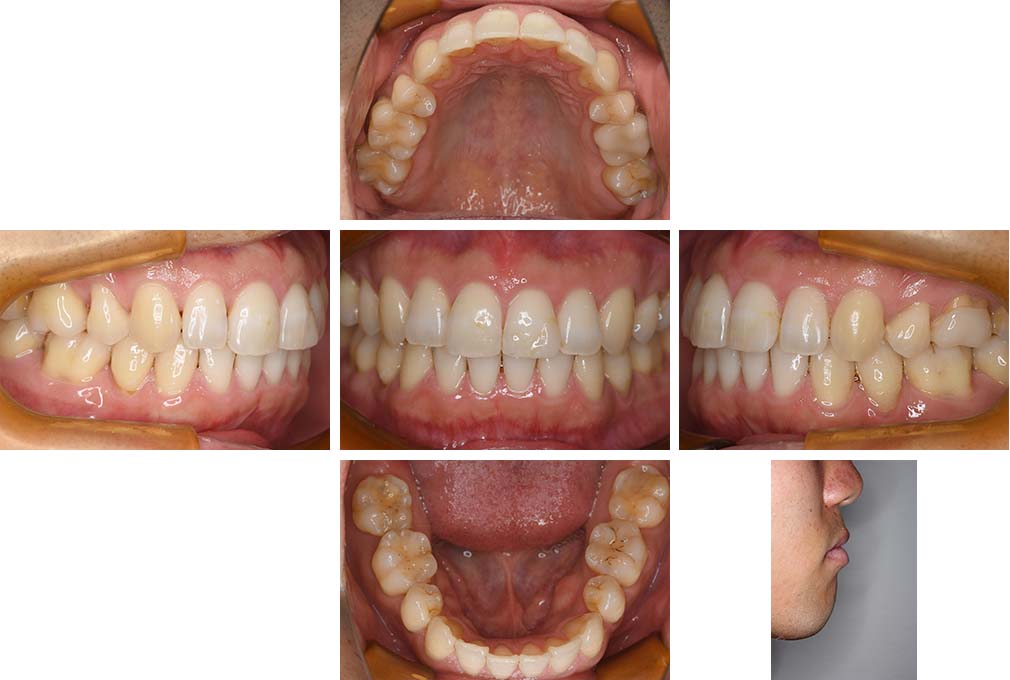

CASE:04

アングルⅢ級傾向を持つ叢生

初診時年齢 22歳

性別 女性

治療費の目安 105万円程度(治療開始時)

上顎右側犬歯が唇側に転位していることを主訴に県内歯科医院から紹介来院された。骨格的にはⅢ級傾向で上顎右側犬歯が唇側転位となり、側切歯が口蓋側に転位していた。下顎前歯が叢生になっていることも相まって上下の正中線は右側に大きくずれていた。アングルⅢ級傾向を持つ上下顎前歯部叢生と診断した。

上下顎小臼歯を抜歯していただき上顎舌側、下顎唇側マルチブラケット装置を使用して動的治療を行った。矯正用ゴムの使用など協力状態も良く、正中線の大きな移動があったのも関わらず2年10カ月で装置を撤去し保定へ移行した。保定移行後14年が経過し、ご息女の診察でご来院いただいていたことから、口腔内を拝見したが、下顎前歯のわずかなずれがあったものの大きな歯列の乱れはなく歯列は安定していた。動的治療期間2年10カ月間。

治療前

22歳6か月

治療後

動的治療期間2年10カ月間

25歳6か月

治療終了

動的治療終了後2年2カ月

28歳8か月

14年経過

動的治療終了後14年7カ月

40歳1か月